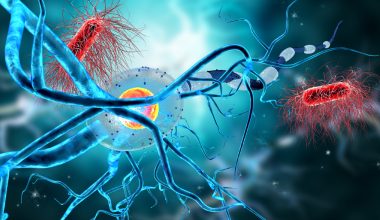

Η διάγνωση ενός όγκου στον εγκέφαλο μπορεί να γίνει με καθυστέρηση, καθώς είναι πιθανό τα συμπτώματά του να αποδοθούν σε κάποιο άλλο πρόβλημα υγείας.

Περίπου 9.000 άνθρωποι κάθε χρόνο διαγιγνώσκονται με όγκο στον εγκέφαλο, εκ των οποίων περίπου οι μισοί είναι καλοήθεις και οι άλλοι μισοί κακοήθεις.

Σε κάποιες περιπτώσεις ο όγκος αναπτύσσεται πολύ αργά. Πρόσφατη έρευνα που εξέτασε τις αλλαγές στη λειτουργία του ανοσοποιητικού συστήματος, έδειξε ότι τα κακοήθη γλοιώματα μπορεί να χρειαστούν ακόμη και πέντε χρόνια για να γίνουν κλινικά εμφανή.

Η έγκαιρη ανίχνευση του καρκίνου στο κεφάλι, αυξάνει τις πιθανότητες αποτελεσματικής θεραπείας.

Δυστυχώς, σύμφωνα με τη Δρα Deborah Lee, συχνά παρατηρείται καθυστέρηση στη διάγνωση, καθώς τα συμπτώματα μπορεί να είναι παραπλανητικά και να αποδίδονται σε άλλες καταστάσεις.

«Στο πλαίσιο μελέτης που πραγματοποιήθηκε το 2019, οι συγγραφείς πήραν συνεντεύξεις από 39 ασθενείς με όγκους στον εγκέφαλο και τις οικογένειές τους και διαπίστωσαν ότι τις περισσότερες φορές, οι ασθενείς εμφάνισαν μια σειρά από ανεπαίσθητες ενδείξεις και όχι έντονα συμπτώματα τους μήνες πριν από τη διάγνωσή τους».

Τα σημάδια αυτά ήταν:

- Αλλαγές στη γραφή

- Αλλαγές στην ομιλία

- Αλλαγές στην κατανόηση

- Αλλαγές στη μνήμη

- Αλλαγές στη συγκέντρωση

- Αλλαγές στην παράλληλη εκτέλεση εργασιών (multitasking)

- Δυσκολίες στον ύπνο

- Μη φυσιολογική αίσθηση στο κεφάλι

- Πονοκέφαλοι

- Ζάλη

Η Δρ. Λι πρόσθεσε: «Οι συγγενείς τους ανέφεραν ότι έχασαν το ενδιαφέρον τους για τις καθημερινές δραστηριότητες και σταδιακά σταμάτησαν να ασχολούνται με τους ανθρώπους και το περιβάλλον τους. Είναι ζωτικής σημασίας να αυξηθεί η ευαισθητοποίηση για αυτά τα συμπτώματα τόσο για τους γενικούς ιατρούς όσο και για τους ασθενείς».

Καθώς ένας όγκος εγκεφάλου μεγεθύνεται, αυξάνει την πίεση στο εσωτερικό του εγκεφάλου, προκαλώντας μια σειρά άλλων συμπτωμάτων.

Αυτά μπορεί να περιλαμβάνουν:

- Πονοκεφάλους (το άτομο ξυπνάει συνήθως το πρωί με πονοκέφαλο, ο οποίος είναι έντονος και επίμονος)

- Ναυτία και εμετούς

- Θολή όραση

- Υπνηλία

- Επιληπτικές κρίσεις

- Αλλαγές στη συμπεριφορά και την προσωπικότητα

Νευρολογικά συμπτώματα, όπως δυσκολία στην ομιλία, προβλήματα όρασης ή/και παράλυση που επηρεάζουν τη μία πλευρά του σώματος.

Η Δρ. Lee εξηγεί: «Όταν ένας όγκος στον εγκέφαλο προκαλεί συμπτώματα αυξημένης ενδοκρανιακής πίεσης, είναι πιθανό να έχει προχωρήσει αρκετά και να προκαλεί απόφραξη στη ροή του εγκεφαλονωτιαίου υγρού (ΕΝΥ) γύρω από τον εγκέφαλο και το νωτιαίο μυελό. Τα ακριβή συμπτώματα και σημεία του όγκου εξαρτώνται από τη θέση του όγκου μέσα στον εγκέφαλο, το μέγεθος και τον τρόπο με τον οποίο πιέζει τις γύρω δομές».

Αν έχετε κάποια από τα παραπάνω συμπτώματα, επισκεφθείτε γιατρό.

Η συντριπτική πλειοψηφία των ανθρώπων με αυτά τα συμπτώματα δεν έχουν όγκο στον εγκέφαλο. Εάν όμως ξυπνάτε με επίμονους πονοκεφάλους ή έχετε ανεξήγητη ναυτία και εμετούς που επιμένουν, μην αμελείτε τα συμπτώματα.